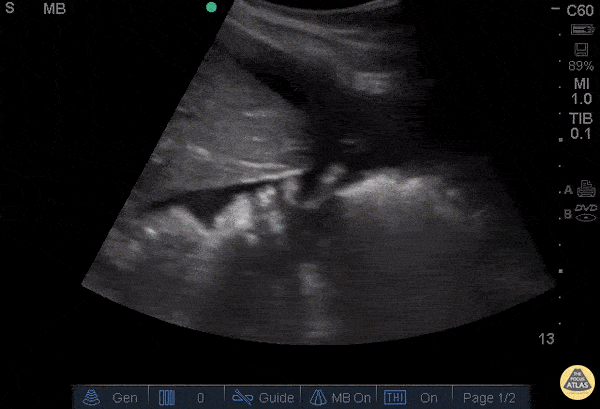

OB/Gyn - Positive FAST in RUQ - Ruptured Ovarian Cyst

28 year-old female was BIBEMS after a witnessed syncopal episode at home. The patient endorsed abdominal pain that started during intercourse that morning and had been getting worse. On arrival, the patient appeared pale and diaphoretic. The patient’s FAST exam was performed immediately and showed free fluid in the RUQ and LUQ. The suprapubic view showed a large pelvic hematoma. The patient was evaluated by the GYN service and was taken emergently to the OR where she was found to have a ruptured cyst. Don't forget, the FAST can be used for more than trauma. Dr. Guru Shan and Dr. Catherine Bon - Kings County Emergency Medicine